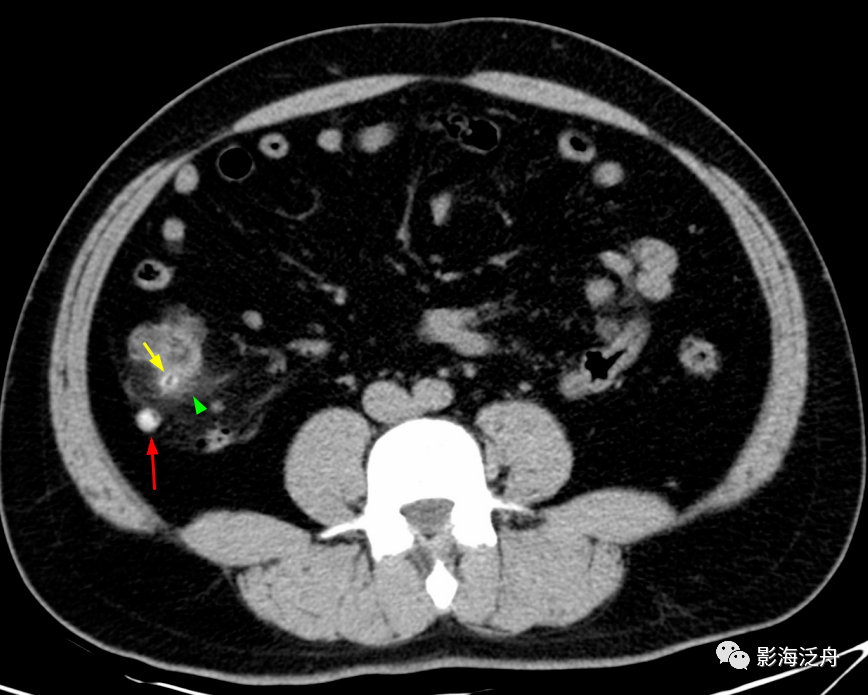

盲肠前壁的憩室炎,憩室内含高密度粪石影(红箭头),离憩室最近的地方即

盲肠憩室内环形粪干(红箭),憩室周围无渗出;盲肠憩室内结节状粪石